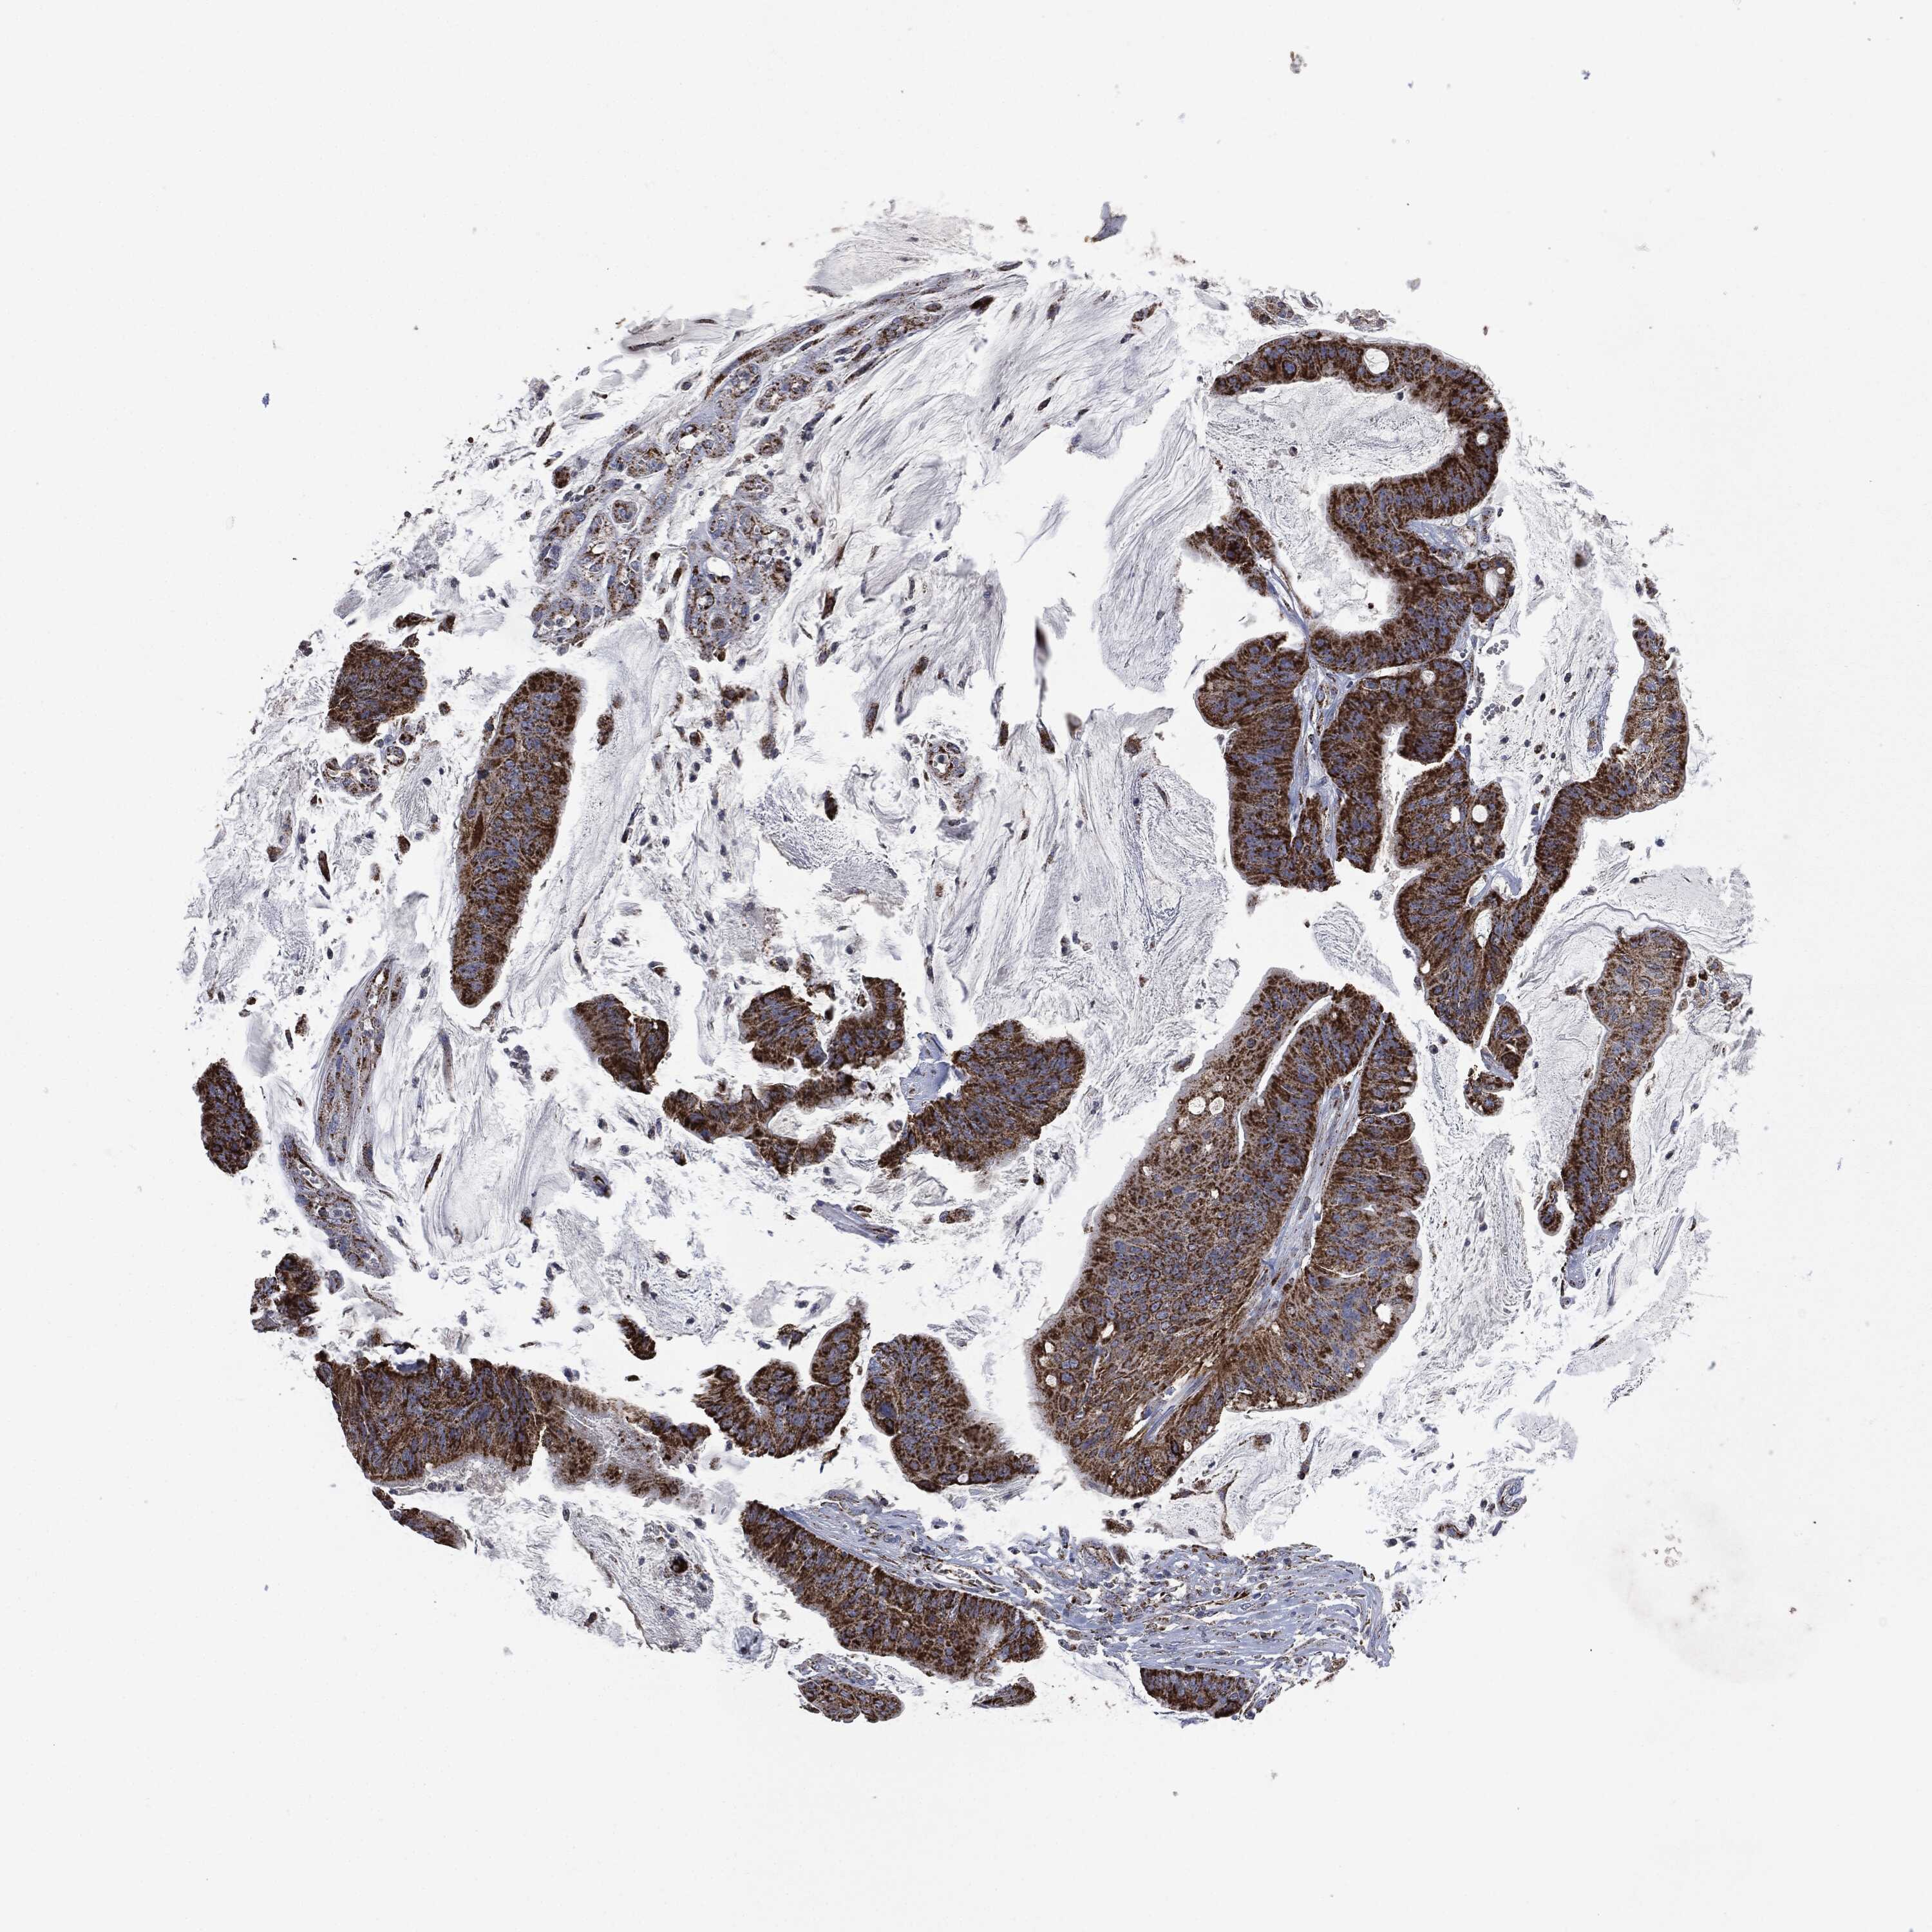

CANCER COLORECTAL CANCER Show tissue menu

Colorectal cancer

Human cancer

Colon adenocarcinoma

Rectum adenocarcinoma